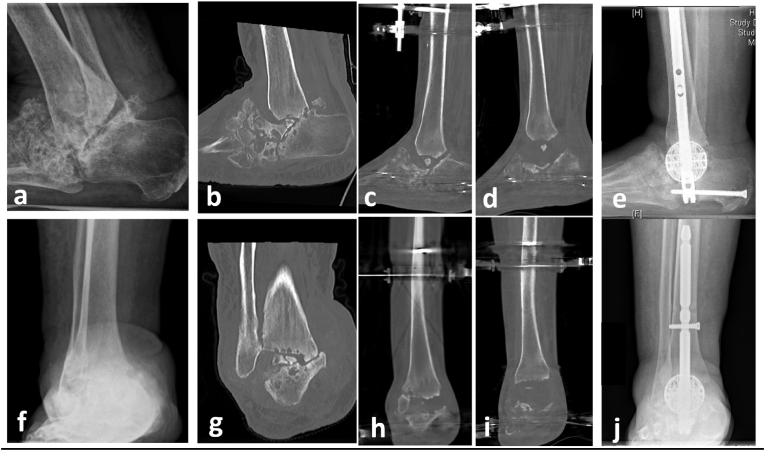

Fig. 2.

a-e) Xray and CT of a 60 year old male with hindfoot Charcot Neuroarthropathy with osteomyelitis. f-h) Xray and CT scan demonstrating circular frame external fixation in insitu for acute tibial-calcaneal fusion with use of intraosseous antibiotic bone substitute within the tibia and calcaneus. i) j) 12 weeks fluoroscopy post removal of circular frame external fixation demonstrating a tibial-calcaneal arthrodesis.